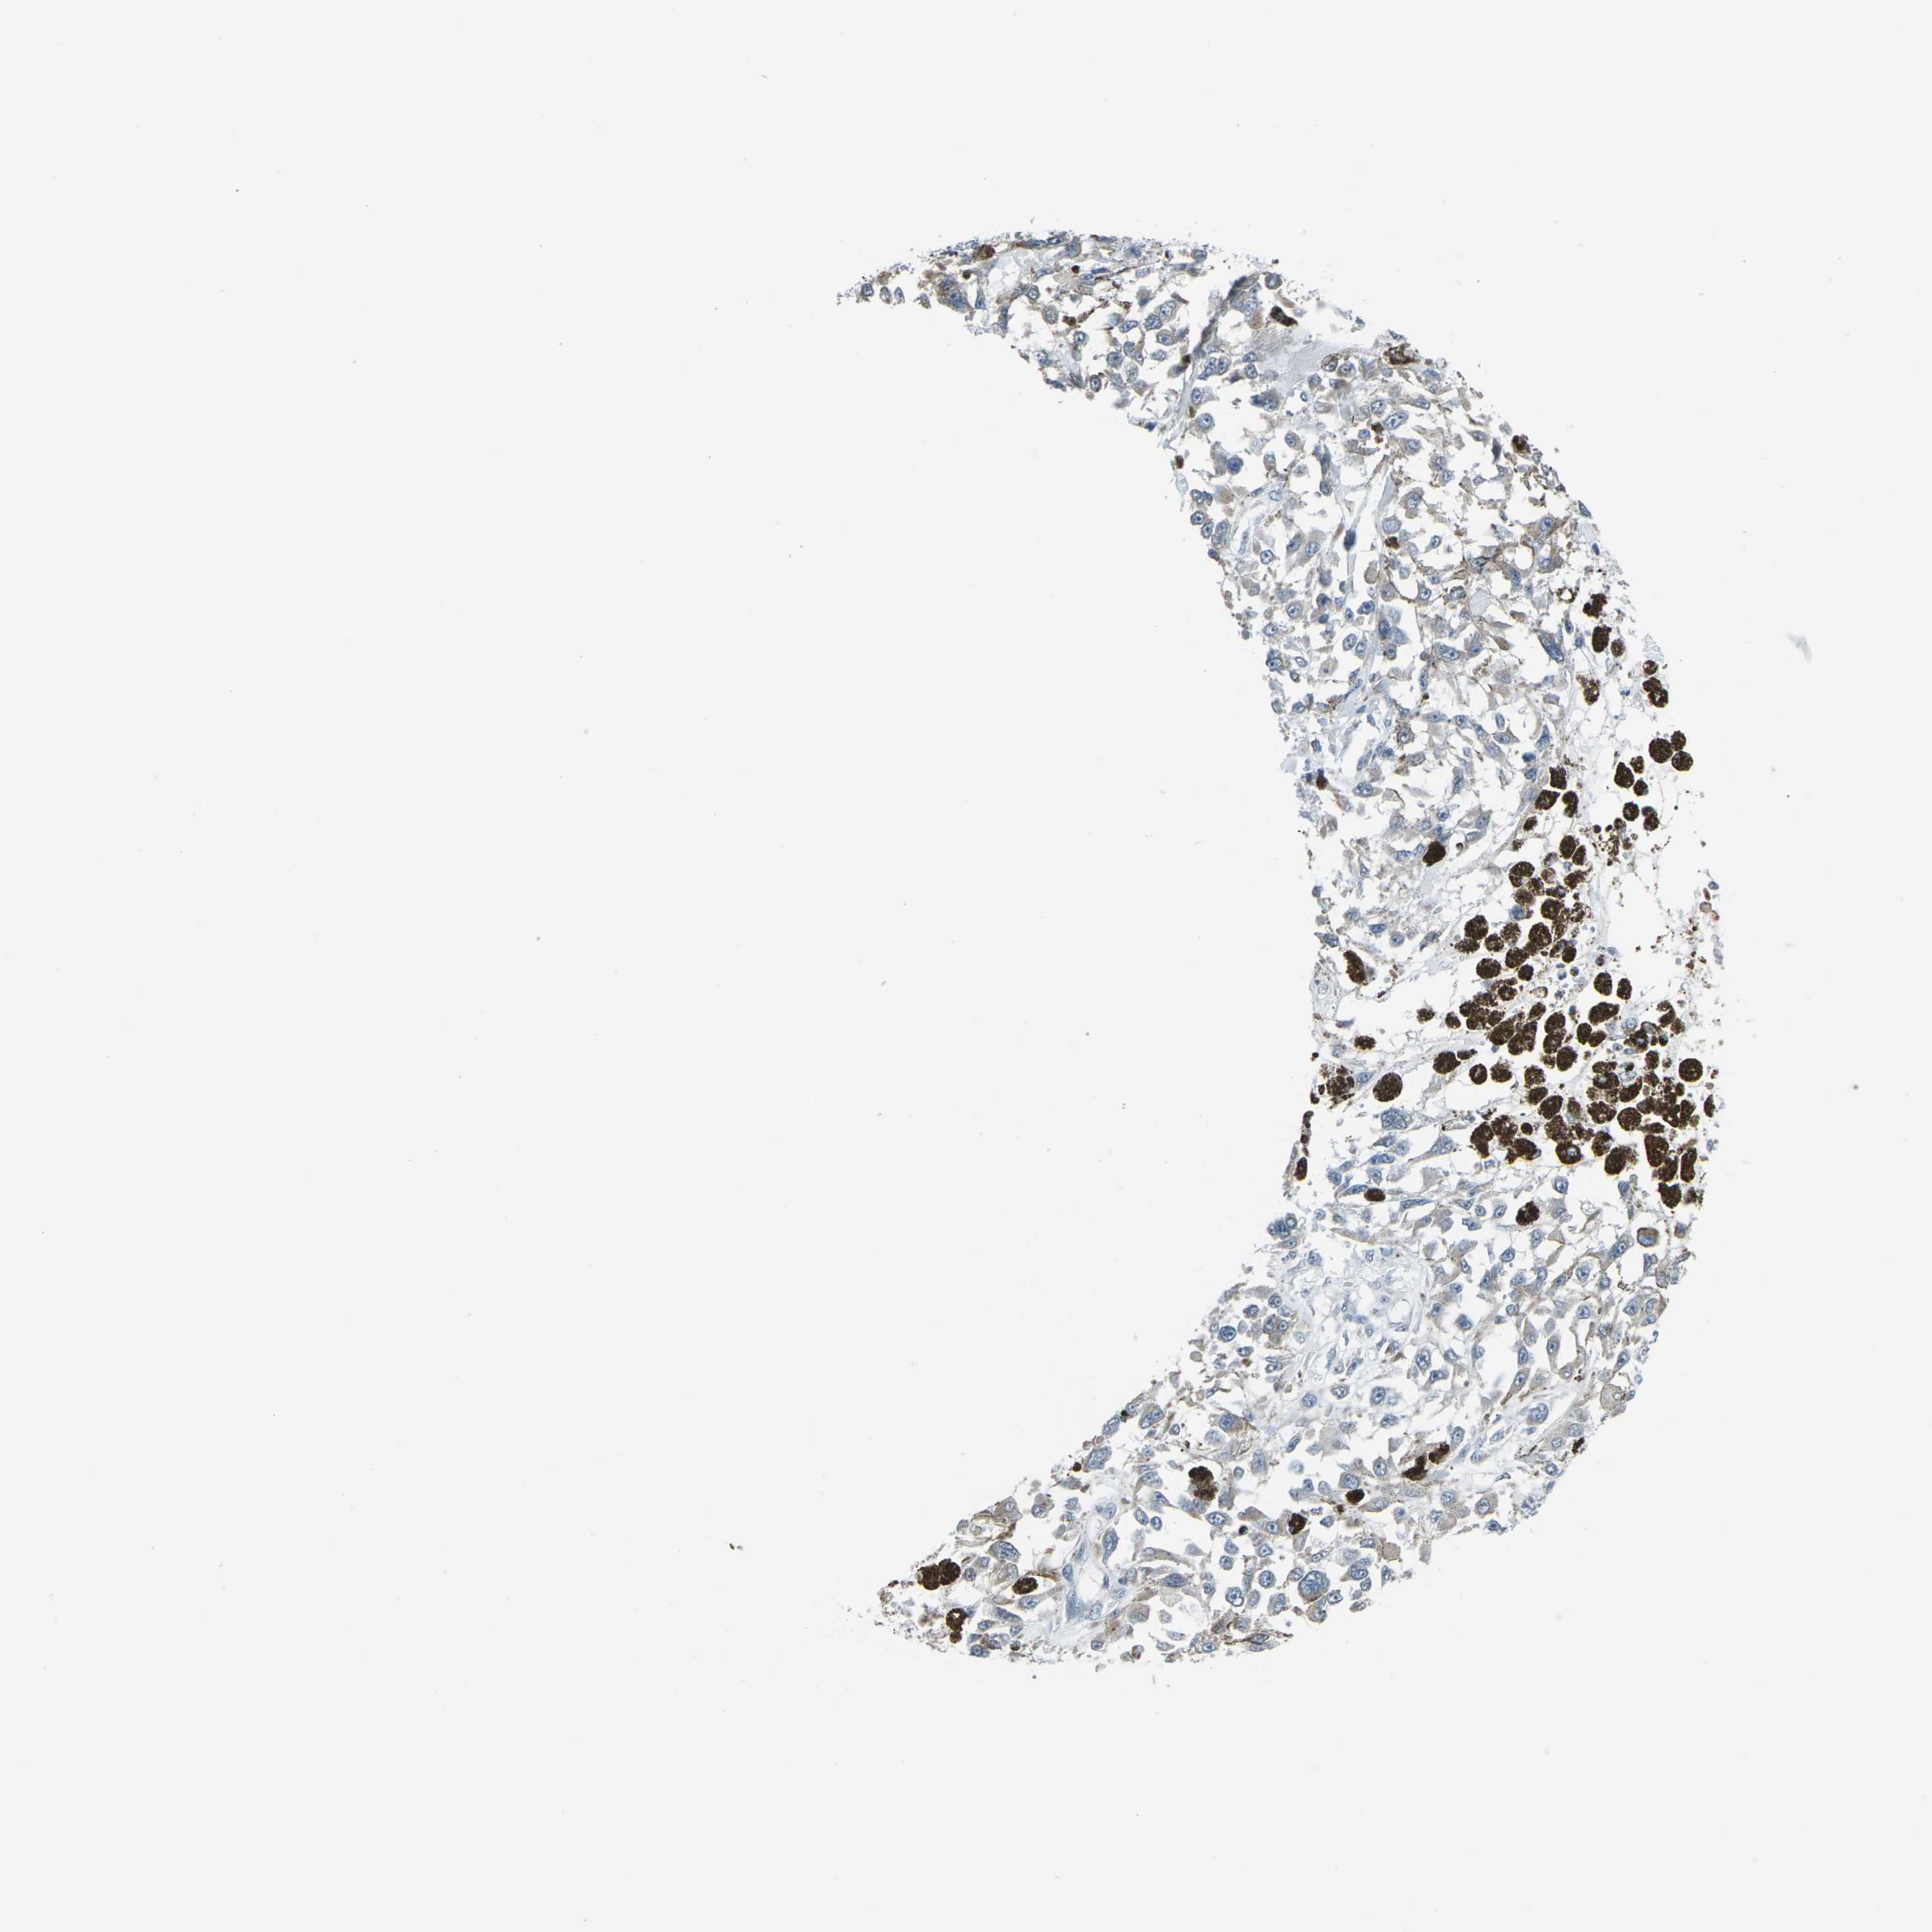

MELANOMA - Protein expressioni

A mouse-over function shows sample information and annotation data. Click on an image to view it in a full screen mode. Samples can be filtered based on level of antibody staining by selecting one or several of the following categories: high, medium, low and not detected. The assay and annotation is described here.

Note that samples used for immunohistochemistry by the Human Protein Atlas do not correspond to samples in the TCGA dataset.

Antibody stainingi

Antibody staining in the annotated cell types in the current human tissue is reported as not detected, low, medium, or high, based on conventional immunohistochemistry profiling in selected tissues. This score is based on the combination of the staining intensity and fraction of stained cells.

Each image is clickable and will lead to virtual microscopy that enables deeper exploration of all samples and also displays staining intensity scores, fraction scores and subcellular localization as well as patient and tissue information for each sample.

Antibody HPA042205

Antibody HPA043013

Antibody CAB011603

Staining

High

Medium

Low

Not detected

Intensity

Strong

Moderate

Weak

Negative

Quantity

>75%

75%-25%

<25%

None

Location

Nuclear

Cytoplasmic/membranous

Cytoplasmic/membranous,nuclear

Malignant melanoma, NOS

Malignant melanoma, Metastatic site

Malignant melanoma in situ